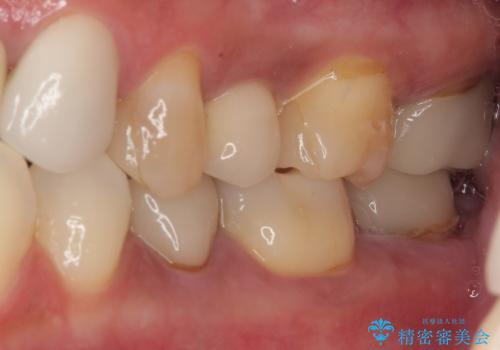

右下のむし歯が歯肉縁下に及んでおり、歯周外科処置(歯冠長延長術)を行った上で、根管治療を行い、状態を整えて補綴治療を行うこととしました。

上顎前歯の根尖病変に痛みがありましたが、既に前歯が補綴治療済みであっため、外科的歯内療法(歯根端切除術)を行うことで解決することとしました。

新幹線で通院をされていたため、極力診療回数を減らして、一度にまとめて多くの処置を行うことで負担を軽減しました。